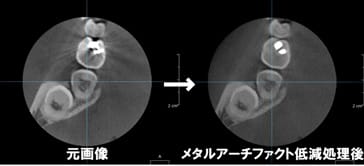

歯科領域において高分解能画像の撮影が可能です。任意の断面画像・3D画像の作成が可能で、撮影後の画像データに処理を行うことで、メタルアーチファクト低減処理ができます。

全く新しい画像再構成法O-MAR(Metal Artifact Reduction for Orthopedic implants)により、金属による画像への影響を抑制した診断に有用な画像を迅速に提供します。